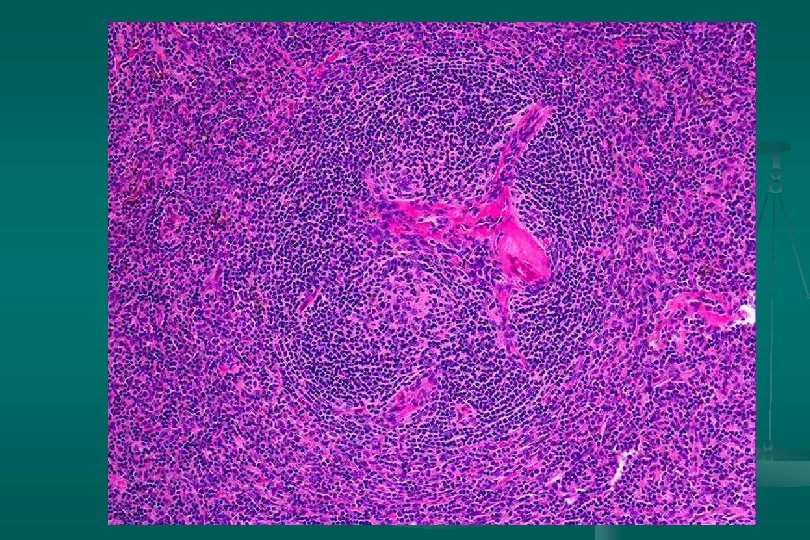

Enfermedad de Castleman Histología: dos categorías: 1. Tipo vascular hialino (angiofolicular): n Folículos grandes, proliferación vascular y hialinización central. n Capas concéntricas de linfocitos en la periferia del folículo (capas de cebolla). n Estroma interfolicular: prominente, venulas poscapilares hiperplásicas, CP, E. inmunoblastos n

Enfermedad de Castleman Subtipo linfoide: *Expansión zona del manto *Centros germinales pequeños. 2. Tipo células plasmáticas: n Proliferación difusa de cels plasm interfolicular + cuerpos de Russell n Cambio vascular-hialino: ausente n Depósito de material acidofílico amorfo (fibrina y complejos inmunes) n